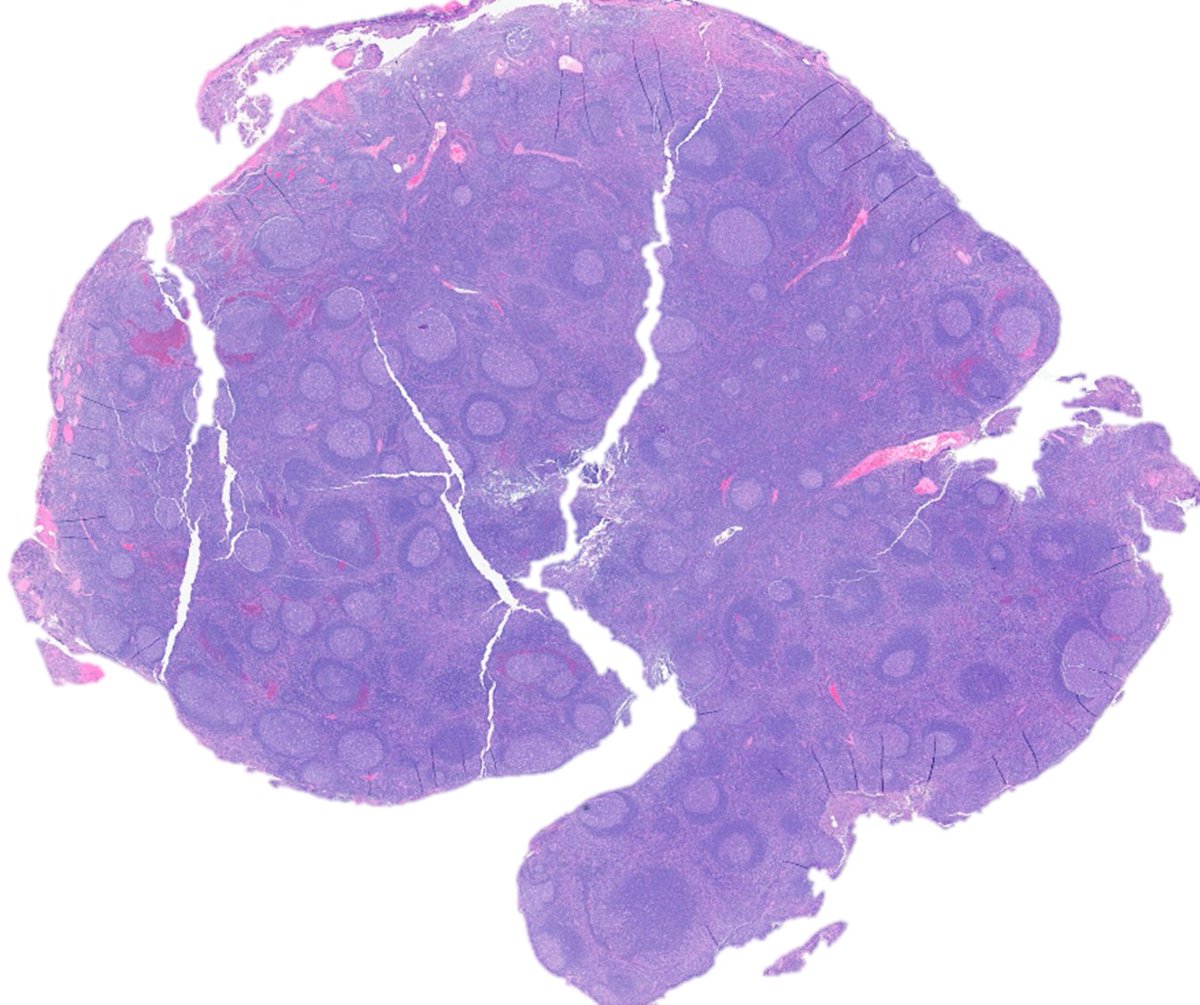

Rare sighting of "focal" primary large B-cell lymphoma of the testis in action, slowly making its way to seminifrous tubules #Hemepath #Lymsm #Pathtwitter #PathX #Sugpath #MedED